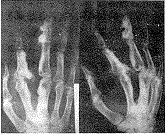

蜡泪样骨病(Melorhostosis Leri)是一种罕见的骨病,又可称为肢骨纹状增生症、烛泪样骨质增生、单肢象牙性骨质增生症、流动性骨硬化症等 ......